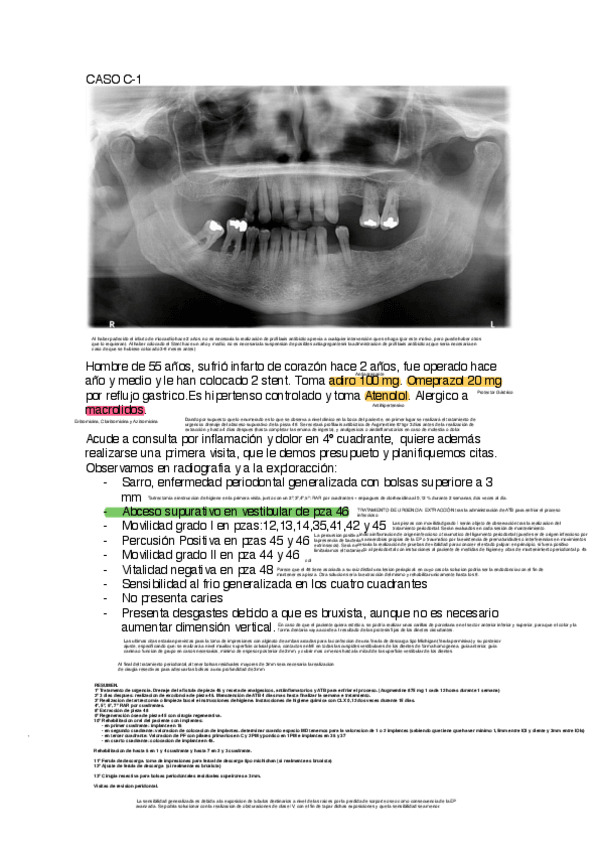

CASOS CLINICOS REPASO

He publicado nuevos ejercicios de 5º CLÍNICA INTEGRADA II: CASOS CLINICOS REPASO